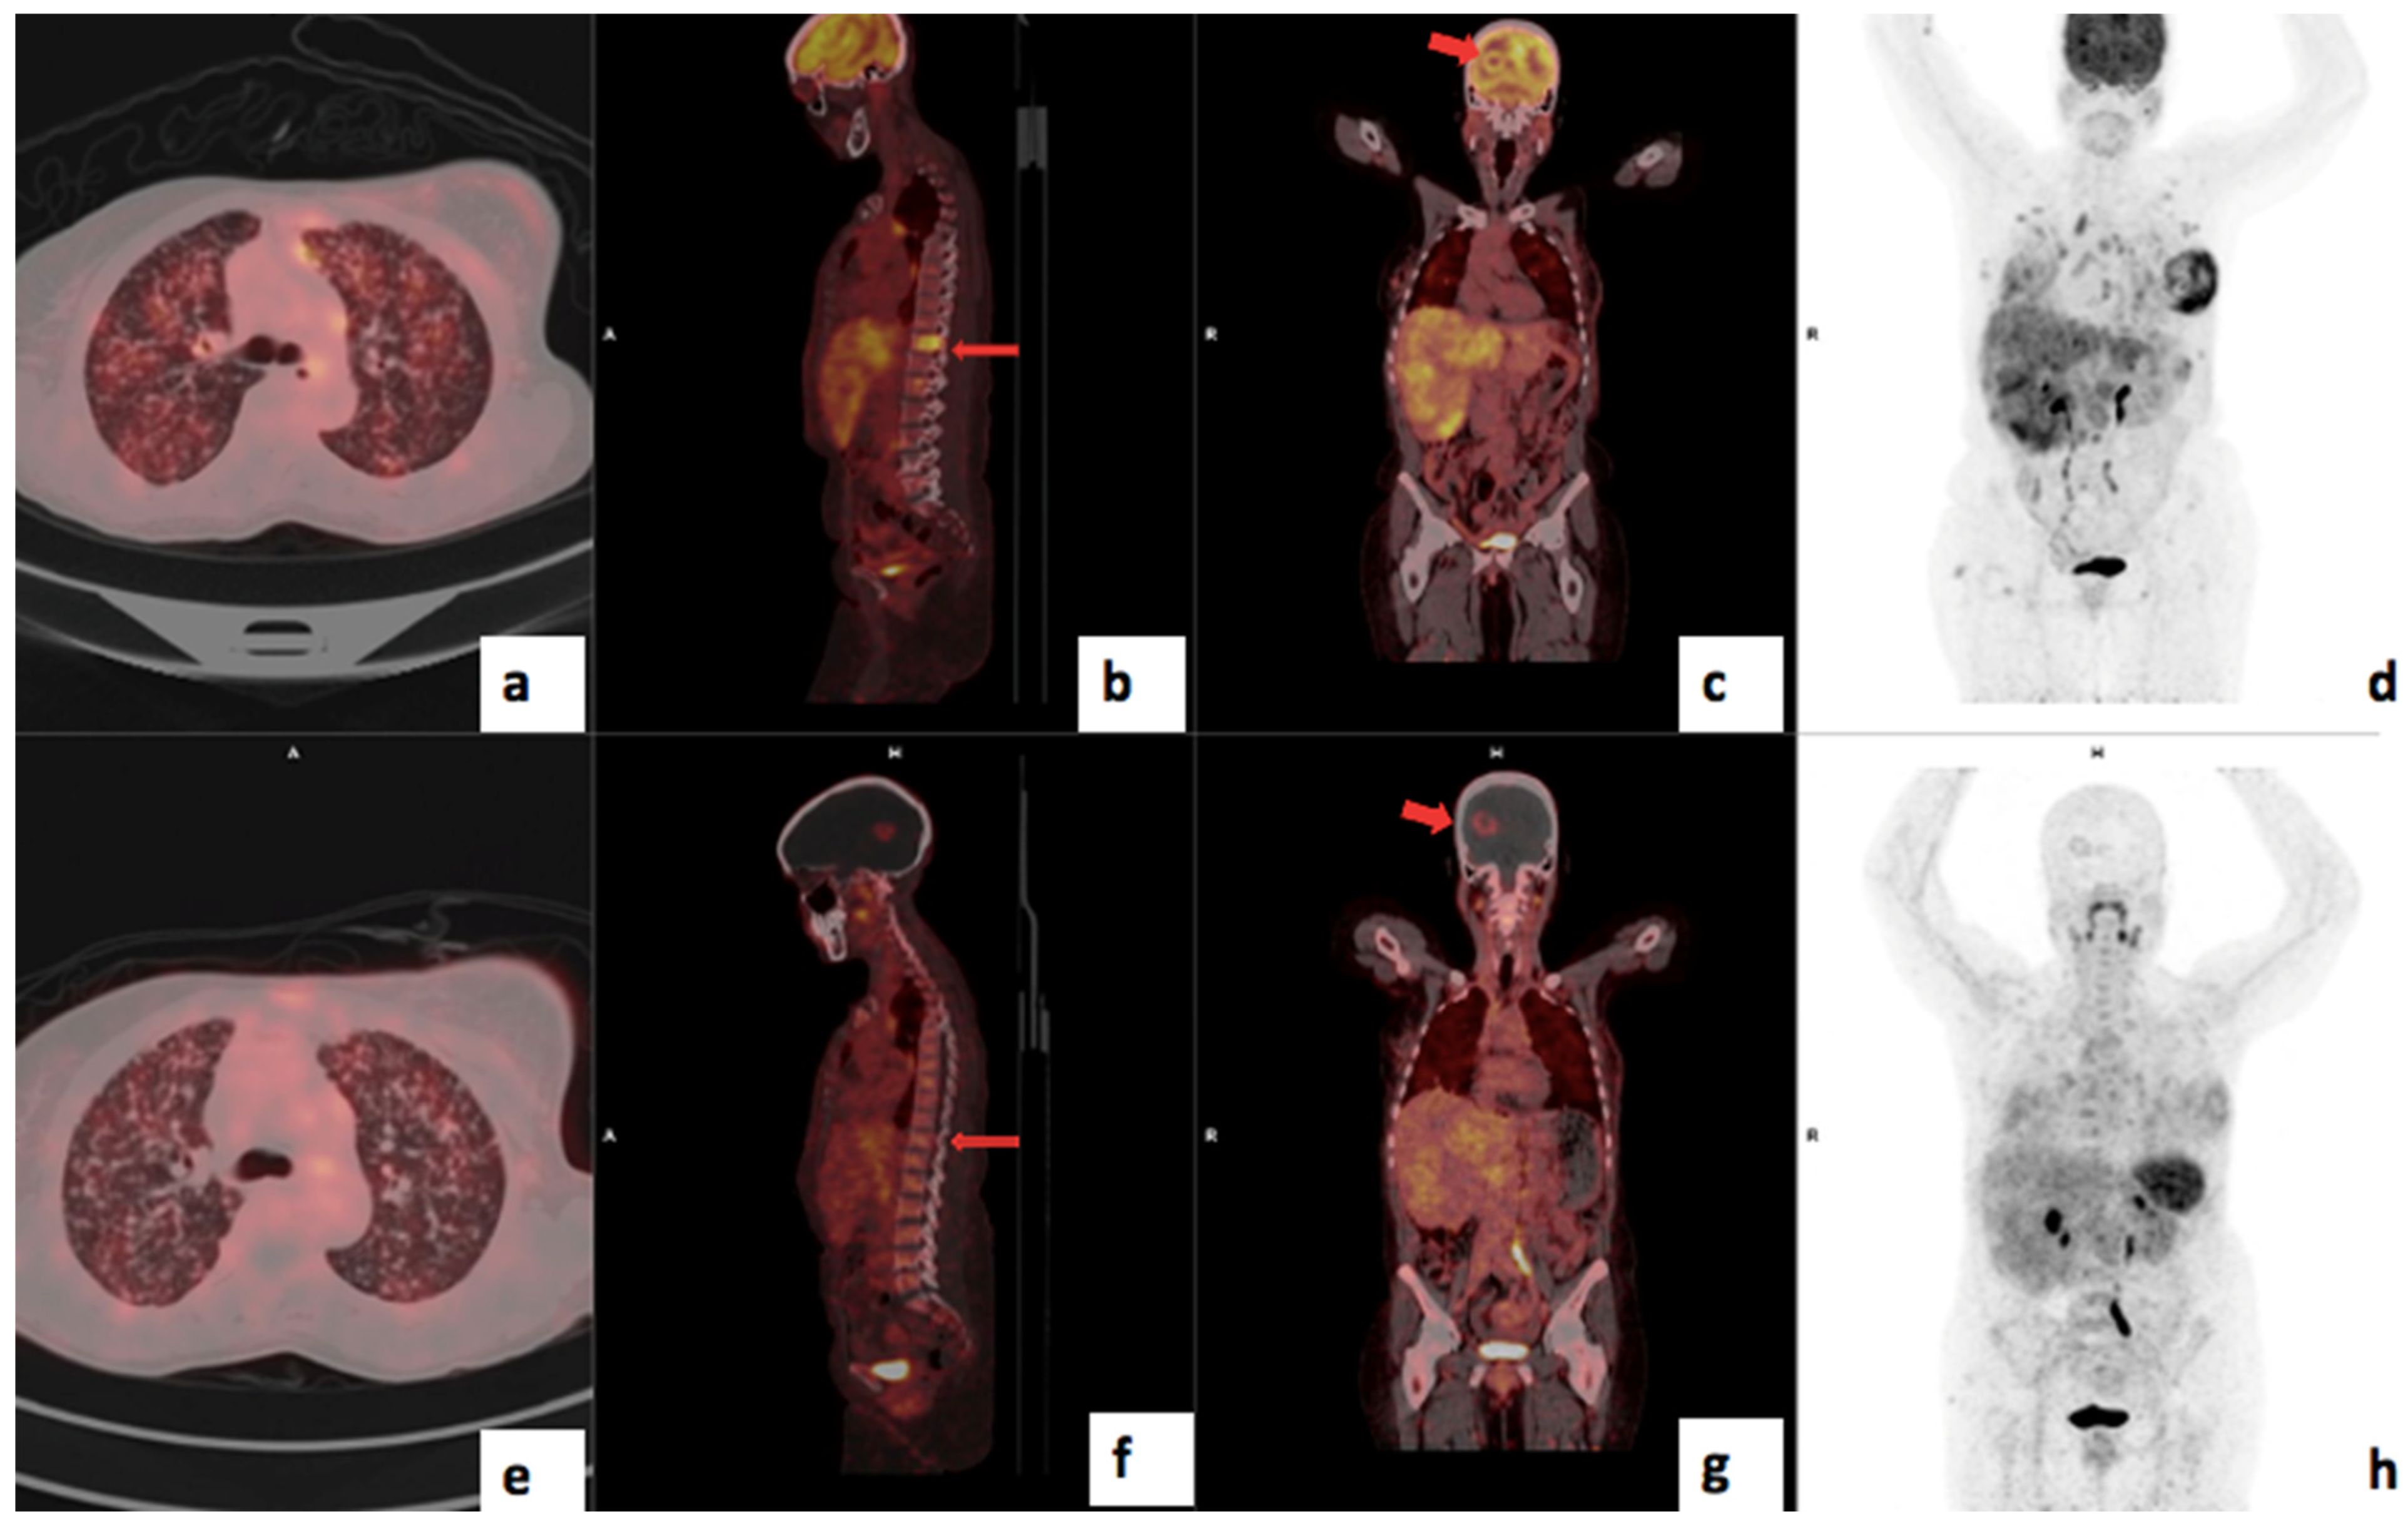

Figure 9.

A 48-year-old female with left T3N1M1 breast cancer showing increased heterogeneous uptake in the left breast primary (SUVmax 13.1), with brain, liver, lung and skeletal metastasis using 18F-FDG PET/CT (a–d). The lesions are seen on 68Ga-Pentixafor (e–h) but appear less intense (SUVmax 4.26). The brain lesion is more visible using Pentixafor (g) due to lower brain uptake than FDG (c) and the vertebral lesion is more visible on FDG (b) than Pentixafor (f) due to higher physiological marrow uptake (h).

In addition, because of the less intense physiological uptake of 68Ga-Pentixafor in the brain, this novel tracer allows for better visualization of metastasis in the skull and brain, as demonstrated in Figure 6. This is in agreement with findings by Buck et al. [25]. As the brain is an obligate user of glucose, there is a high physiological uptake of FDG, which may obscure both intracranial and skull lesions. However, 68Ga-Pentixafor, similar to [18F]-FDG, also accumulated in reactive lymph nodes, and therefore, the biopsy of suspicious lymph nodes remains invaluable for confirmation of metastatic spread, especially in areas outside the normal/expected lymphatic drainage of the breast. 68Ga-Pentixafor missed skeletal metastasis in the spine in two patients likely due to the high physiological bone marrow accumulation of this tracer; an example is shown in Figure 9. The high but variable physiological uptake on 68Ga-Pentixafor is due to CXCR4 expression on hematopoietic stem cells and progenitor cells in the bone marrow [26]. Further, it is possible that the high bone marrow accumulation of 68Ga-Pentixafor is attributed to an immune response triggered by stress signals originating from peripheral tissues, which subsequently activate the bone marrow [26]. Solid tumors, including breast cancer, induce a state of chronic inflammation that causes myelopoiesis in the bone marrow.

Figure 10.

A 73-year-old with luminal A T4cN2M0 Bloom Richardson Grade III right breast cancer, demonstrating very mild uptake in the right breast and overlying soft tissue: SUVmax 2.9 using 18F-FDG (c,d) and 4.04 using 68Ga-Pentixafor (g,h). Notably, FDG detected skeletal metastases (a,b) that were missed using 68Ga-Pentixafor (e,f). CXCR4 expression was mild in 15% of the tumour cells on IHC staining.

The 68Ga-Pentixafor SUVmax for TNBC was higher than the luminal subtypes in this current study; however, this did not reach statistical significance due to the modest sample size. The median 68Ga-Pentixafor PET/CT SUVmax values in patients with luminal A, luminal B, HER2-enriched and triple-negative disease were 5.24 (4.26–7.18), 5.45 (4.30–7.09), 5.10 (4.18–7.40) and 7.10 (5.95–9.63), respectively (p = 0.224). Figure 9 shows an example of a patient with luminal A molecular subtype breast cancer with very low avidity in the breast primary and skeletal disease using 68Ga-Pentixafor; the lesions are clearly visible using 18F-FDG. This is in agreement with a study by Vazquez et al. who demonstrated a higher CXCR4 expression in triple-negative samples compared to in luminals A and B and HER2-enriched in the molecular subtype analysis of breast cancer tissue RNA sequencing data from the Cancer Genome Atlas (TCGA) breast cancer cohort [33].